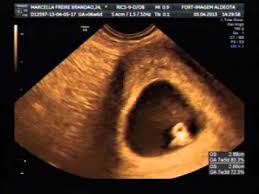

Ultrassom 7 Semanas De Gestacao Youtube

1ª Ultrassonografia 7 Semanas 2 Dias